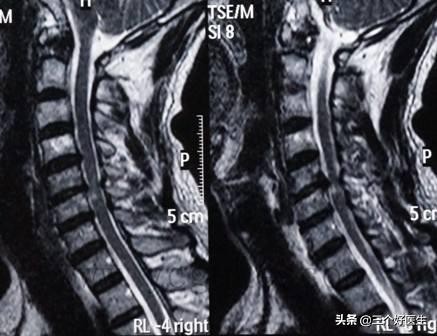

第三个阶段已经进入到了退变的中期了,椎间隙变窄,椎间盘突出,缩水,硬化,脊椎的关节功能受限但还没有完全丧失,神经受压迫的现象明显且持续。该阶段对应的年纪大约在40~65岁.

MR显示C4/5/6/7椎间盘突出,且椎间盘缩水严重,硬膜囊受压。

第三阶段需要做到防治结合,防大于治。通过正骨治疗尽可能的改变脊椎神经的受压,尽可能的恢复关节的功能性运动,维护退化的脊椎关节功能,保护未退化的关节。